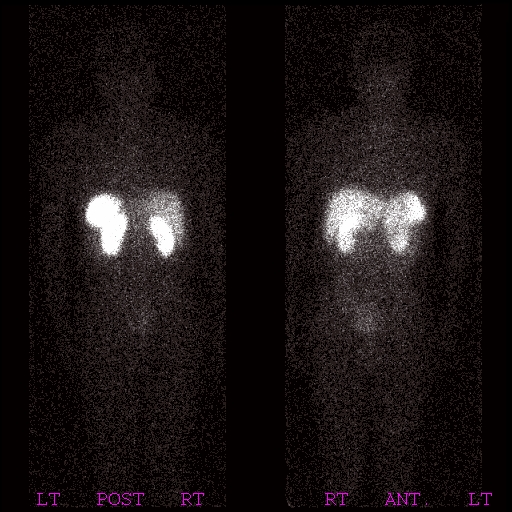

這題我在 94年第1次高考第8題有作了完整的說明,另外在讀者服務區的核醫導讀中的2.5.9.1 Radiolabeled Peptides放射性標幟的peptides中也有說明,在核研所取得販賣In-111 octreotide的許可證後,恰好我們腸胃科轉介了一位懷疑是胃腺體癌的病人,我們在打完針後15分鐘,4、24小時都做了掃描,同時也做了SPECT,只是似乎沒有什麼發現,這項檢查有幾個需要注意的地方,藥物的排泄主要是經由腎臟,因此打針後必須大量喝水,一方面是保護腎臟,一方面是避免腎臟聚積太多活性,剩下的會經由腸道排泄,因此也必須讓病人吃吃輕泄劑,把腸道的活性去除,值得注意的是,這種藥物在脾臟有相當強的聚積,因此脾臟是受輻射暴露最高的器官,下面是檢查的影像。

15分鐘

4小時

24小時

局部的影像